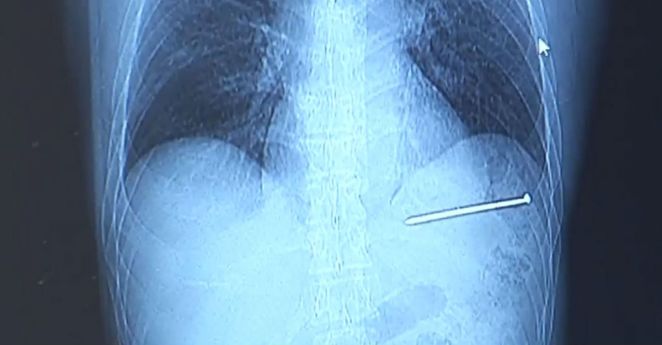

This Guy Accidentally Shot Himself In The Heart With A Nail Gun and Then Drove Himself to The Hospital